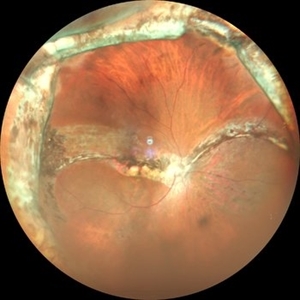

Wide Field Image of Fundus Coloboma

Aug 31 2019 by Gayathri Mohan

Wide field color photo of fundus coloboma post PPV for RD. laser marks seen.

Photographer: Dr. Gayathri Mohan, Retina Foundation

Imaging device: Mirante,Nidek

Condition/keywords: coloboma